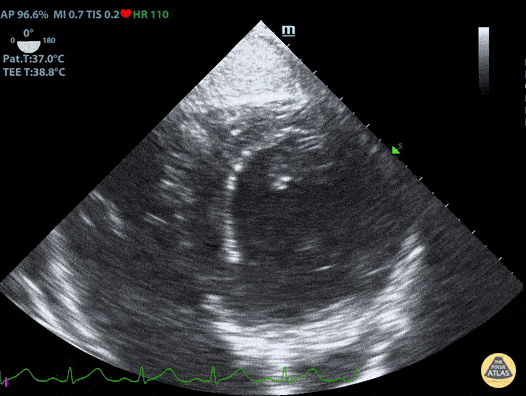

Normal Trans-Gastric Short Axis View Duncan McGuire, DO, Emergency Medicine, Beaumont Health

https://www.thepocusatlas.com/tee